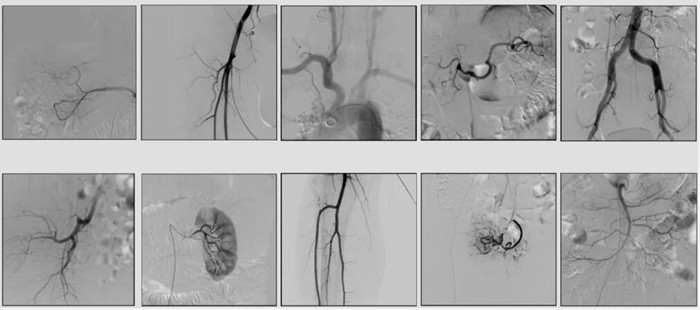

2)中C,學名外周介入C形臂(Peripheral Interventional C-Arm)。與小C相比,中C不僅大幅提高了X射線系統功率,更重要的是增加了減影等血管機相關功能,基本可以完成80%的介入手術需求,主要應用在周圍血管科、消化內科、婦科、整形科等領域。

中C在周圍血管領域有重要價值